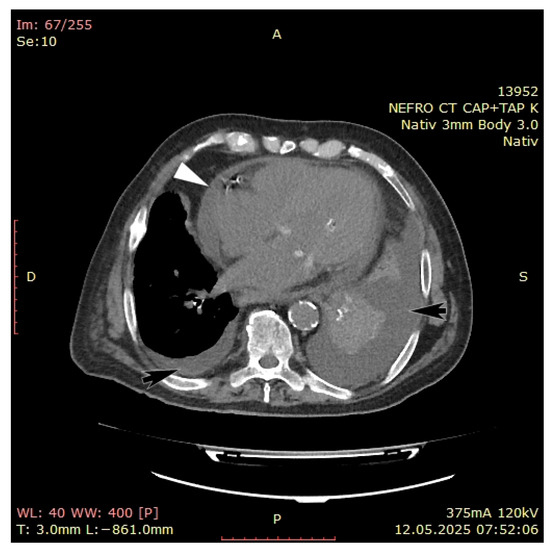

3. Case Presentation